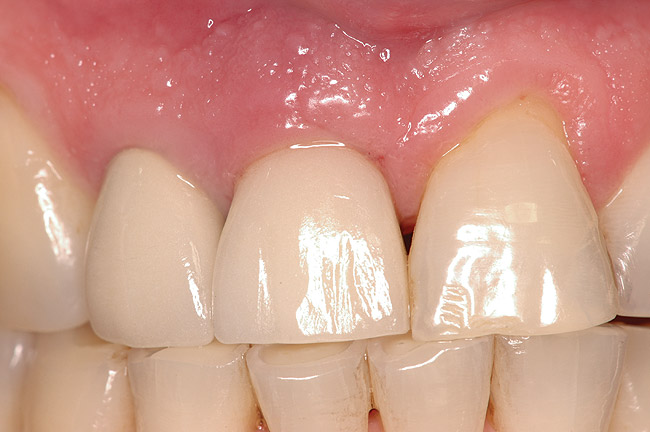

Figure 15  Final restoration of the replacement implants. Left central incisor and right and left lateral incisors were restored with individual tooth-supported single crowns.

Figure 15

The patient returned regularly for recall visits for 7 years, but then did not return for follow-up or maintenance for 2 years. He then returned for evaluation and retreatment of the implant. However, retreatment was not possible as the bone loss and lesion morphology were unfavorable for attempting a regenerative approach (Figure 14). The implant was removed atraumatically, and the site was grafted with a composite graft of mineralized and demineralized freeze-dried bone allograft and covered with an absorbable porcine collagen barrier. The flap was advanced to enable primary closure of the site and it was allowed to heal for 6 months. Re-entering the site, the bone fill achieved by the regenerative efforts enabled a second implant to be placed in a favorable prosthetic position (Figure 15 and Figure 16).